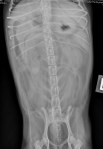

Latérale gauche